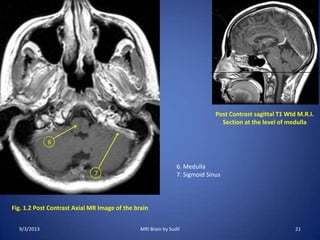

Fig. 1.2 Post Contrast Axial MR Image of the brain

Post Contrast sagittal T1 Wtd M.R.I.

Section at the level of medulla

6. Medulla

7. Sigmoid Sinus